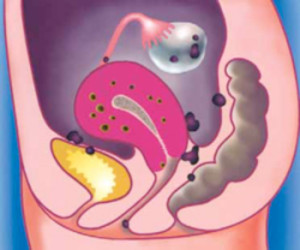

Внутренний генитальный эндометриоз (аденомиоз матки) — это гинекологическая патология, при которой эндометрий (ткань, выстилающая матку изнутри) прорастает в мышечный слой матки (миометрий). Заболевание диагностируется у женщин 25-40 лет. На начальной стадии развития генитальный эндометриоз склонен протекать бессимптомно. А при отсутствии качественного лечения болезнь может приводить к таким осложнениям, как бесплодие, кисты яичников, менструальные кровотечения и нарушения цикла.

Болезнь часто сочетается с другими формами эндометриоза, опухолями и кистами яичников, миоматозными узлами матки, эндокринологическими отклонениями. Заболевание требует проведения тщательной диагностики, так как для аденомиоза матки характерны симптомы, которые наблюдаются и при других гинекологических нарушениях.